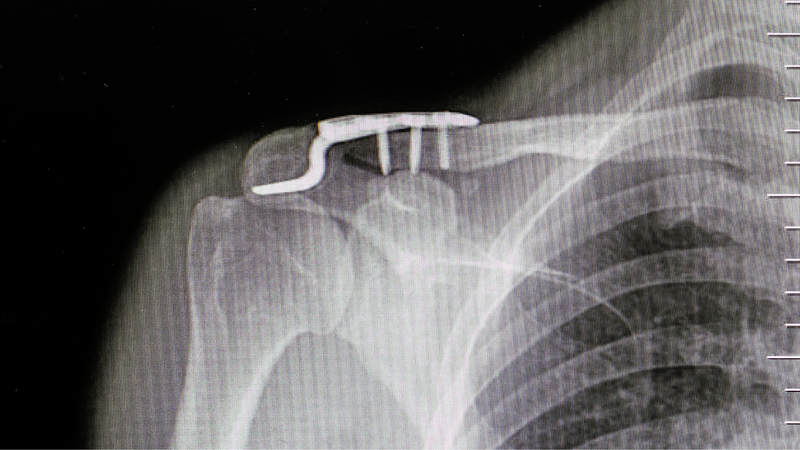

Nẹp xương đòn, hay còn gọi là nẹp cố định xương đòn, là phương pháp điều trị phổ biến cho các trường hợp gãy xương đòn. Nẹp được làm từ các tấm kim loại và đinh vít, có tác dụng cố định và nắn chỉnh vị trí xương gãy, giúp xương lành lại nhanh chóng và đúng vị trí. Tuy nhiên, bên cạnh những ưu điểm, nẹp xương đòn cũng tiềm ẩn một số rủi ro cần được lưu ý trước khi quyết định sử dụng phương pháp này.

Thường thì, các loại nẹp được sử dụng để điều trị gãy xương (gãy xương đòn) được chế tạo từ chất liệu như titan hoặc thép không gỉ. Chúng có chức năng cố định vết thương để xương có thể lành lại nhanh chóng. Tuy nhiên, nếu sử dụng các loại nẹp vít, việc tái khám sau phẫu thuật là cần thiết để bác sĩ có thể đánh giá tiến triển của xương, kiểm tra liệu xương đã liền hay chưa và đảm bảo rằng các vật liệu phụ trợ này đang hoạt động đúng cách và có hiệu quả trong quá trình điều trị.

Sau phẫu thuật sử dụng nẹp kim loại, có thể để các nẹp này trong cơ thể vĩnh viễn mà không cần thực hiện một ca phẫu thuật thêm để lấy ra, đặc biệt là đối với những bệnh nhân lớn tuổi hoặc có nhiều yếu tố nguy cơ khi phẫu thuật. Đối với những bệnh nhân có bệnh lý nền nặng như tăng huyết áp, đái tháo đường, bệnh tim, suy gan hoặc suy thận, việc không tháo nẹp ra có thể được ưu tiên để giảm nguy cơ phát sinh biến chứng do ca phẫu thuật có thể gây ra những hậu quả nghiêm trọng cho sức khỏe của bệnh nhân.